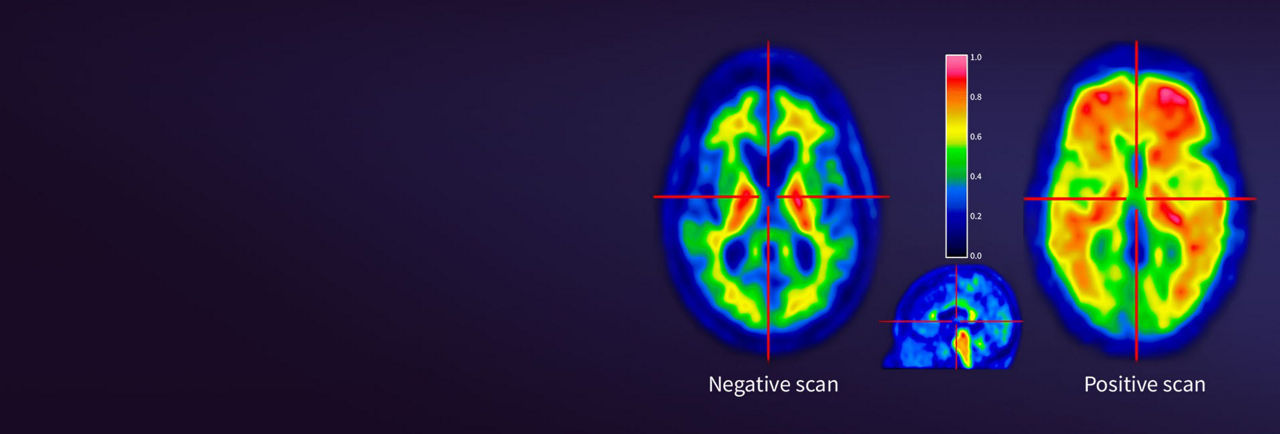

VIZAMYL™ (flutemetamol F 18 injection) is indicated for positron-emission tomography (PET) of the brain to estimate amyloid beta neuritic plaque density in adults with cognitive impairment for:

- Risk of Image Misinterpretation and Other Errors: Errors may occur in the estimation of amyloid beta neuritic plaque density during VIZAMYL image interpretation. The use of clinical information in the interpretation of VIZAMYL images has not been evaluation and may lead to an inaccurate assessment. Extensive brain atrophy and motion artifacts that distort the image may limit the ability to distinguish gray and white matter on a VIZAMYL scan. Perform image interpretation independently of the patient’s clinical information. For cases where there is uncertainty as to the location of cortical signal, use co-registered anatomical imaging to improve localization of signal or examine the striatum for VIZAMYL signal as it is less affected by atrophy.